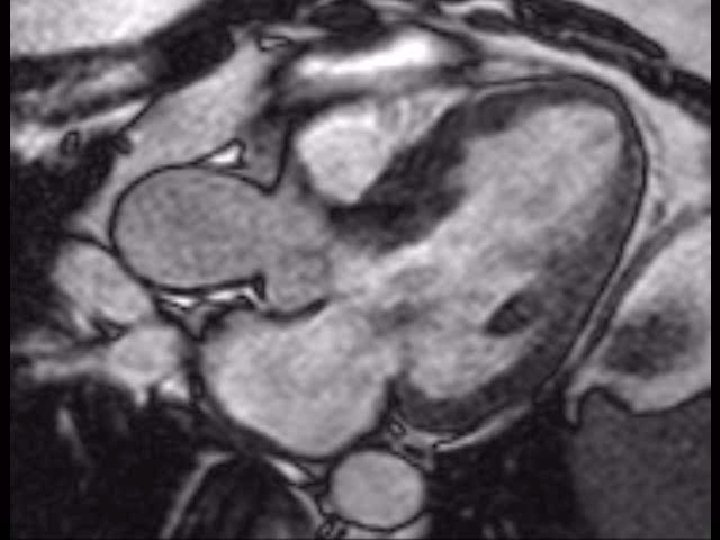

ECHO GRADING OF SAM

Patterns of systolic anterior motion of the mitral valve in hypertrophic cardiomyopathy: assessment by twodimensional echocardiography. –maron et al • In 36 patients (58%), both the anterior and posterior mitral leaflets appeared to participate in SAM. • In 19 patients (31%), SAM was produced selectively by the posterior mitral leaflet. • In only 6 patients (10%) was the anterior leaflet alone responsible for SAM. • In 51 patients (82%), only the distal portion of the anterior or posterior mitral leaflet approached the septum in systole.